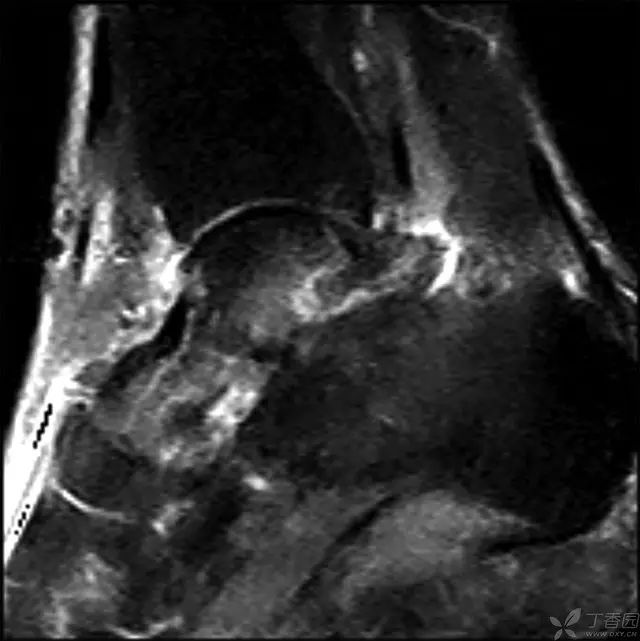

术后 2 周 MRI,没有急性炎症反应

6 个月,有轻度信号改变,表明存在一定程度的生理活动,无骨坏死征象

术后 2 年 MRI,弥漫性信号改变,符合早期骨坏死,但无塌陷

5 年 MRI,弥漫性信号局限在距骨体中心部位,头颈部逐渐出现血运重建,无塌陷